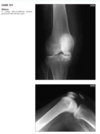

Anteroposterior (Fig. 2.16.1) and lateral

(Fig. 2.16.2) radiographs of the left knee show a semi-

circular lucency, with an adjacent bony fragment,

on the lateral aspect of the medial femoral condyle

(arrows).

sagittal T2-weighted MR

image in the same patient demonstrates minimal

linear increased signal intensity in the same region

as the lucency, located between the subchondral

bone and the fragment (Fig. 2.16.3, arrow). The frag-

ment has low signal intensity and is not completely

covered by cartilage.

Osteochondritis dissecans (osteochon-

drosis) of the medial femoral condyle

from an osteochondral fracture

that was initially caused by shearing, rotatory, or

tangentially aligned impaction forces.

The presence of linear high T2-weighted

signal intensity between the fragment and donor site

indicates fluid or granulation tissue and strongly sug-

gests instability of the fragment (i.e., loose in situ

fragment) (Fig. 2.16.4, arrowheads). Focal cystic areas

beneath the fragment or denudation of articular carti-

lage are also MR signs suggesting an unstable fragment.

All patients with radiographic evidence of osteochon-

dritis dissecans could potentially benefit from MRI to

assess the integrity of the donor fragments before any

surgical or arthroscopic intervention or therapy (71).